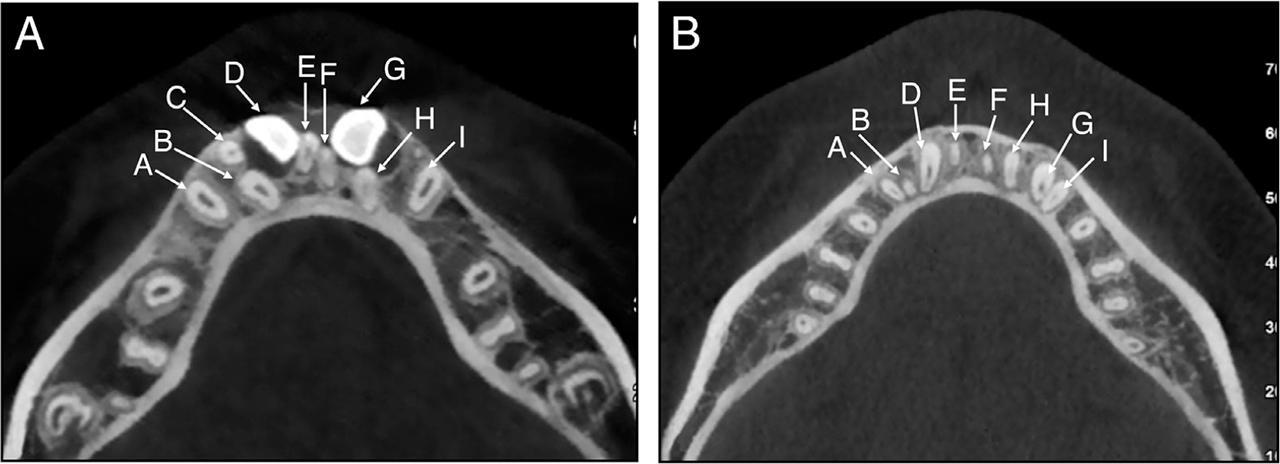

Figure 2